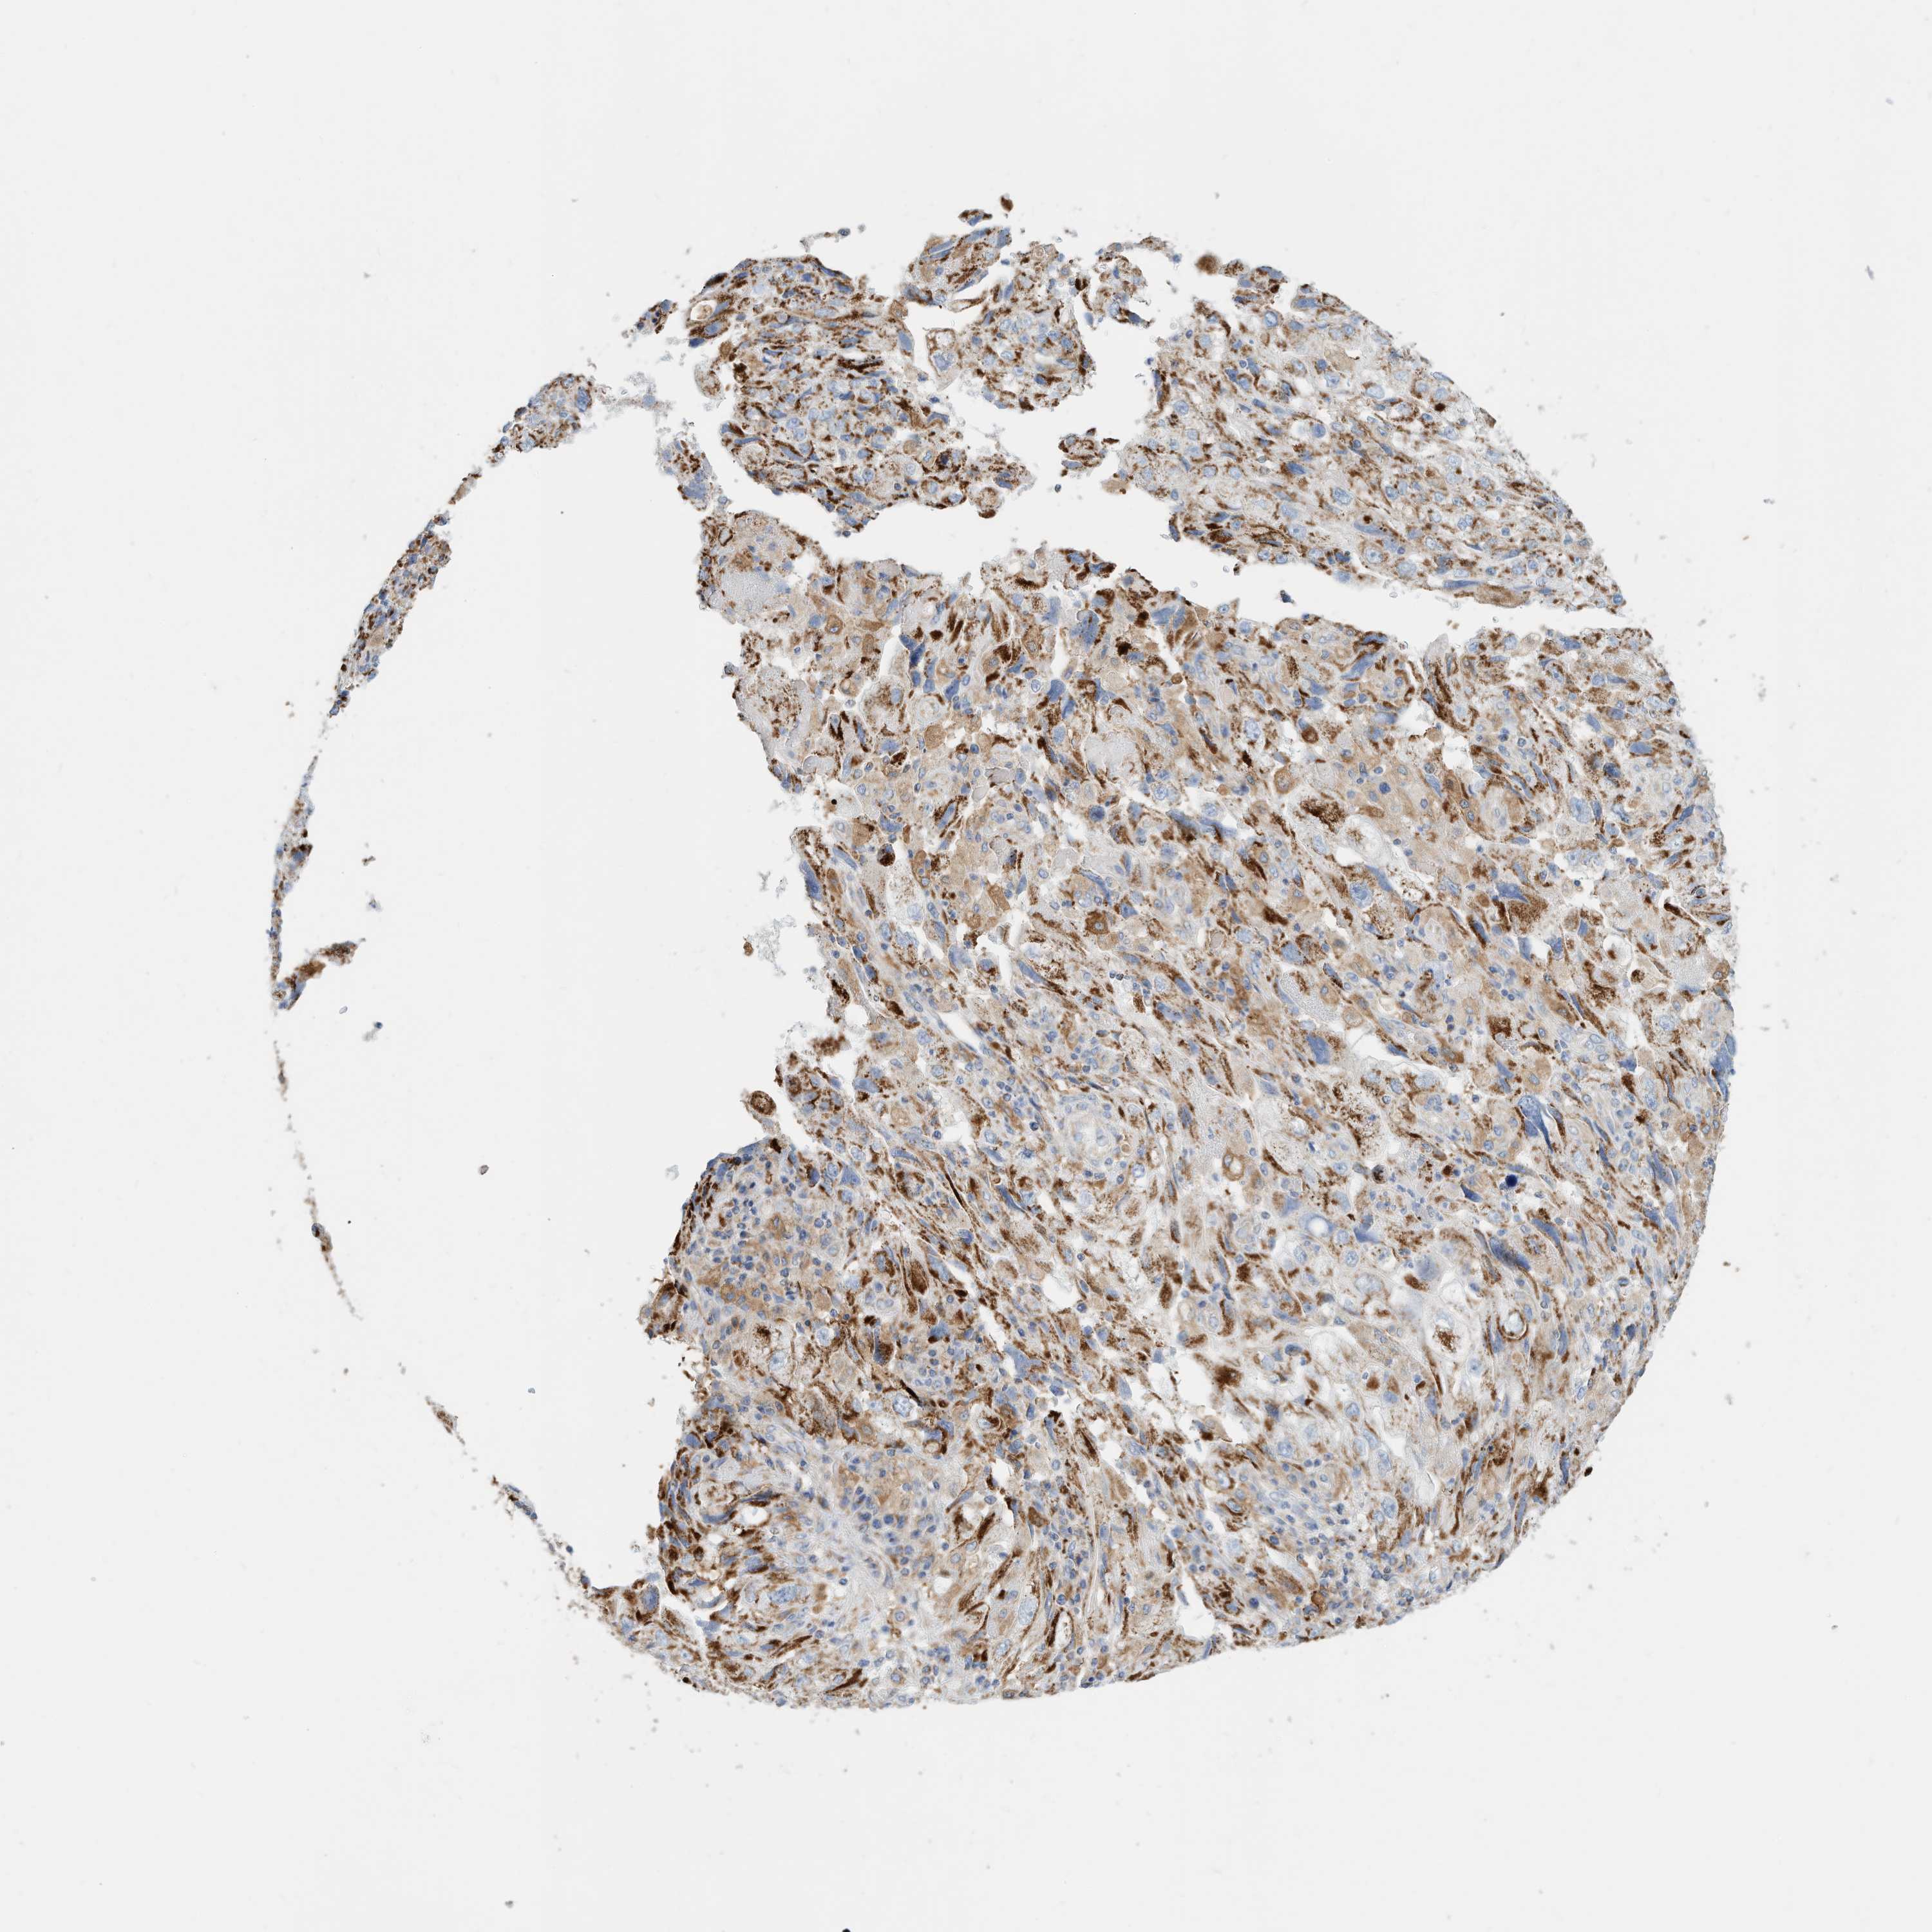

ENDOMETRIAL CANCER - Protein expressioni

A mouse-over function shows sample information and annotation data. Click on an image to view it in a full screen mode. Samples can be filtered based on level of antibody staining by selecting one or several of the following categories: high, medium, low and not detected. The assay and annotation is described here.

Note that samples used for immunohistochemistry by the Human Protein Atlas do not correspond to samples in the TCGA dataset.

Antibody stainingi

Antibody staining in the annotated cell types in the current human tissue is reported as not detected, low, medium, or high, based on conventional immunohistochemistry profiling in selected tissues. This score is based on the combination of the staining intensity and fraction of stained cells.

Each image is clickable and will lead to virtual microscopy that enables deeper exploration of all samples and also displays staining intensity scores, fraction scores and subcellular localization as well as patient and tissue information for each sample.

Antibody HPA030345

Staining

High

Medium

Low

Not detected

Intensity

Strong

Moderate

Weak

Negative

Quantity

>75%

75%-25%

<25%

None

Location

Nuclear

Cytoplasmic/membranous

Cytoplasmic/membranous,nuclear

Adenocarcinoma, NOS

Adenocarcinoma, metastatic, NOS